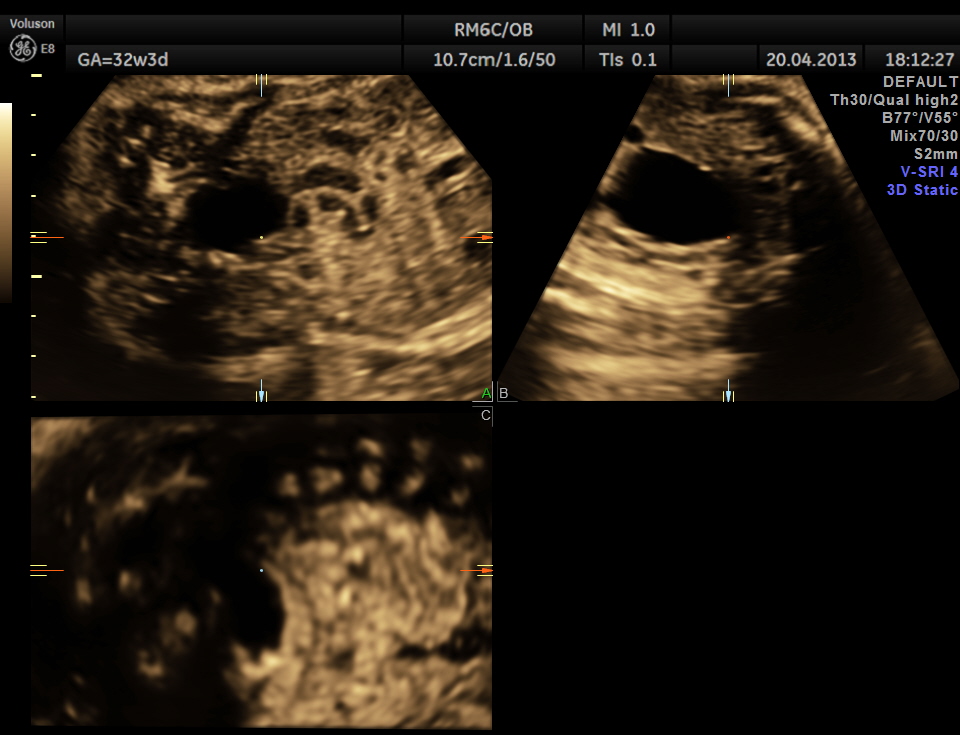

The following images show bilateral renal pelvi ectasis and bilateral dilated ureters with all the changes more in the left kidney .

is it a case of posterior urethral valve

Axial images of kidney would better showed the urethral dilation